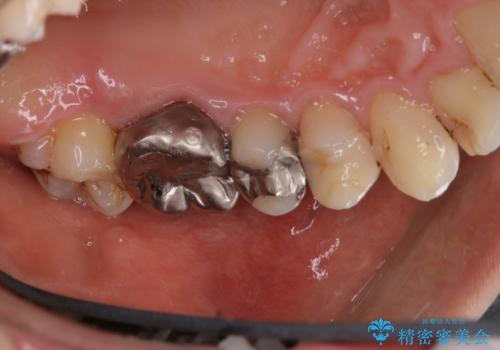

歯の表面に、茶色く色が残っている所がありますが、これは詰め物の変色によるものです。以前に、CR(コンポジットレジン)による虫歯治療がされています。

CRは経年的劣化や、着色してしまうことがあります。PMTCでクリーニングを行うと、古いCRが目立つことがあるため、気になる際は詰め替えを行います。

茶色くなっている部分が、着色なのか、劣化なのか、虫歯によるものなのかは判別が難しいことがあります。そのため、定期的にPMTCを行うことで状態の確認が的確に行えます。